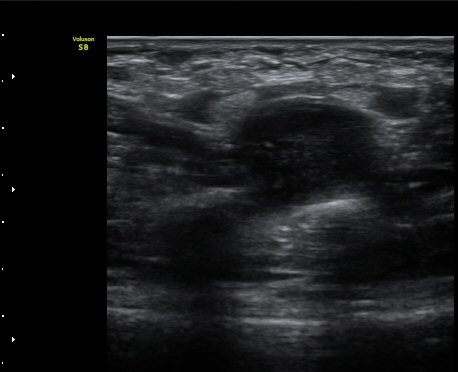

Äá¾Ë»À(pisiform) ºÎÀ§ ô°ñ½Å°æ Ⱦ´Ü¸é°Ë»ç¿¡¼­ Á¤Á߽Űæ°ú ô°ñ½Å°æÀÌ Á¤»óÀûÀÎ ¸ð½ÀÀ¸·Î

°üÂûµÈ´Ù(»çÁø 2).